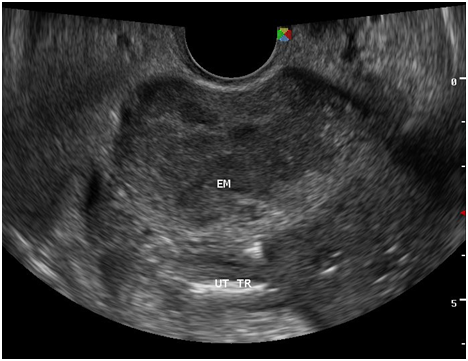

Figure 7 There is a thin midline echogenicity visualized (anteroposterior view), measuring 0.3 cm suggestive of the endometrial lining.

Figure 8 The surrounding myometrium (transverse view) which is hypoechoic, irregular, with scalloping at the periphery with a mixed hyperechoic and echogenic echopattern giving it a marblelized appearance, which may be a unique variation of the usual “moth‒eaten” appearance.

Tuberculous peritonitis is a variant of genital tract tuberculosis. Fallopian tube/uterine disease and tuberculous peritonitis can and does coexist in up to 50% of the cases.22 Tuberculosis is primarily an infection of the respiratory tract. Female genital tuberculosis can develop from a pulmonary nidus of infection or by hematogenous dissemination of organisms and their subsequent localization within the fallopian tube. When the gastrointestinal tract is the portal of infection, involvement of the ileocecal region permits lymphatic spread–primarily to the right fallopian tube.22 The sono graphic findings of this patient described a 5.3x4.6x3.8 cm tubular adnexal mass with scattered echogenic stipplings within, which probably represented tuberculous salpingitis. Myometrial involvement in this patient appeared as irregular scalloping at the periphery of the surrounding hypoechoic myometrium, giving it a marblelized appearance. Dissemination of disease from the fallopian tube occurs by continuous spread to potentially involve the ovary and retrograde into the uterus. Uterine extension involves primarily the endometrium with, at maximum, a 20% incidence of myometrial involvement.22